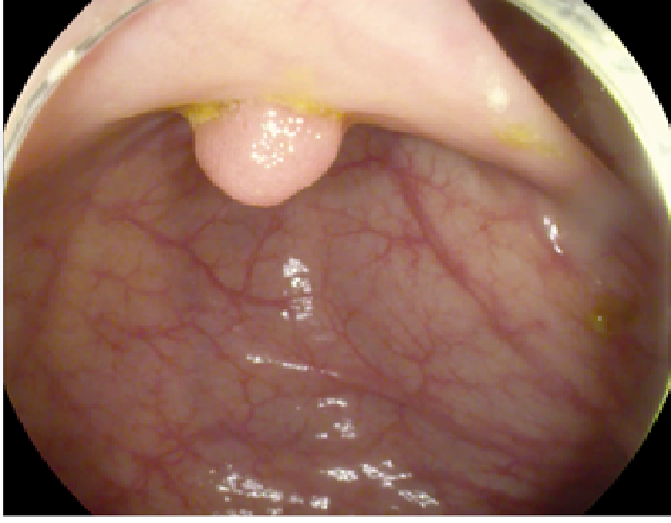

The study used a publicly available dataset of polyp-frames obtained from the ETIS-Larib database [34], containing 196 polyp images. These images were obtained from 34 different colonoscopy videos of 44 different polyps with various appearances and sizes, having a resolution of pixels. The ground truth of polyp areas for polyp datasets is determined by expert video endoscopists. A CNN model trained with such a small amount of data is likely to be meaningless and unstable, so data augmentation was performed on the polyp dataset. Data augmentation had to be performed on the colonoscopy images by considering vivid variations. Otherwise over-fitting would have occurred. In a colonoscopy imagery, polyps exhibits large variations in location, color, and scale. Moreover, variations in brightness and definition also occur due varrying the view-point of the camera. Therefore, in addition to photometric distortions and geometric distortions, we also have considered zooming, shearing, and altering brightness as strategies for data augmentation.

For photometric distortions, we controlled brightness and contrast as an enhancement, while blurring by adding noise with a standard deviation of 1.0. Similarly, for geometric distortions, clock-wise rotation of the polyp images with angles of , , and were performed. Zoom-in and zoom-out with zooming parameters such as 30.00% and 10.00% were performed to obtain different scales of polyp images. Lastly, shearing for both the x-axis and the y-axis was performed to shear the images from left to right and top to bottom, respectively. Fig. 4 shows photometric and geometric forms of image augmentation. In this way, we augmented the data set of the ETIS-Larib database from 196 polyp images to 2,156 images, which is more suitable for training the proposed deep CNN model.

The results shown in Fig. 6 are generated using the proposed deep CNN model on the augmented data set. It can be observed that the proposed model shows better polyp detection performance. As illustrated in Fig. 6, polyps within a frame can be identified at multiple positions, and as noted above in this case, the TP for detection is considered to be 1. The proposed deep CNN model performed better than other benchmark results in terms of the performance metrics listed above, as shown in Table. 2 and Fig. 6.